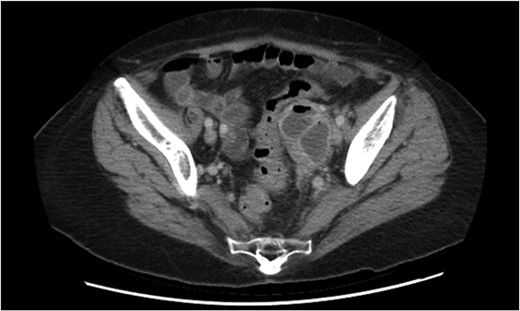

Non-operative management with broad-spectrum IV antibiotics, bowel rest and fluids was trialled. Despite initial clinical improvement with a reduction in pain and down-trending inflammatory markers the patient was once again febrile on day 3 of her admission with plateauing of the inflammatory markers and ongoing pain. A progress CT scan (Fig. 2) showed an unchanged adnexal collection now with sigmoid thickening. Given the findings and lack of clinical improvement, the patient proceeded to have a laparoscopic anterior resection and en bloc left salpingo-opherectomy. Intra-operatively (Figs 3 and 4), the fistula between the sigmoid colon and the left salpinx was very clearly demarcated. Histology confirmed acute diverticulitis locally perforating into the left salpinx and ovary and forming an abscess. An uneventful recovery followed.

Repeat CT scan demonstrating thickening of the sigmoid colon adjacent to the adnexal mass.